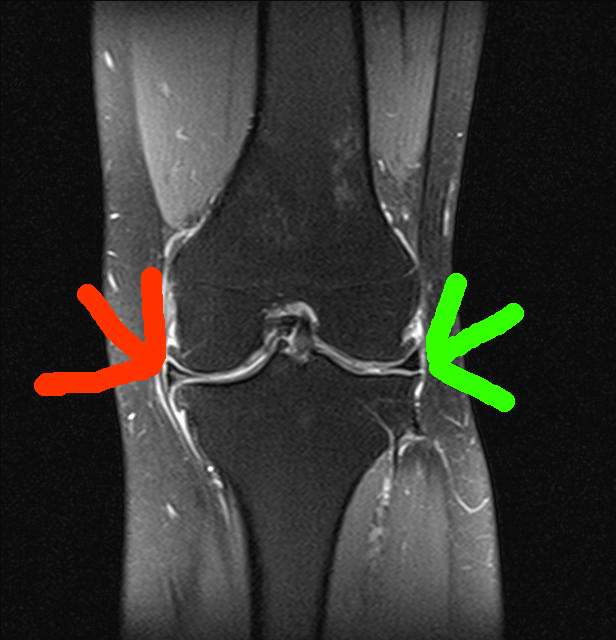

Der Innenmeniskus zeigt auf mehreren Bildern eine Auffälligkeit (Riss, rot markiert). Damals vor der Meniskus-OP am rechten Knie sah das MRT ähnlich aus, rechts ist der Außenmeniskus zu sehen (grüner Pfeil).

Die Kreuzbänder grüne Pfeile sind okay und ein bisschen Athrose (rote Pfeile) ist wohl auch dabei.